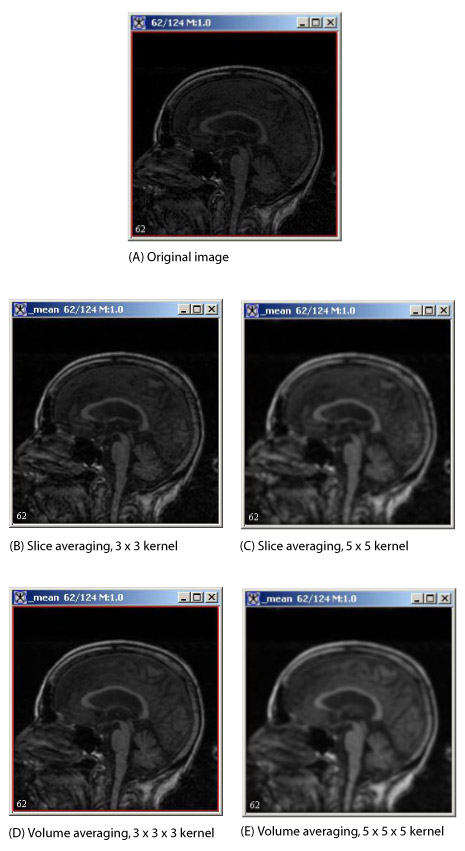

Figure 2. Image processing using the Mean algorithm

This figure depicts slice averaging and volume averaging applied to the whole image with various size kernels as noted.

For slice averaging (Figure 1] and (Figure2), the kernels are odd-length squares (for example, 3 x 3). The processing time increases with the square of the kernel length. For volume averaging ( Figure 2), the kernels are odd-length cubes (such as 5 x 5 x 5), and the processing time increases with the cube of the kernel length. Refer to Figure 2 for examples of slice and volume averaging.